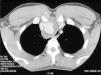

Presentamos el caso de un varón de 26 años, trabajador agrícola, no fumador y sin antecedentes personales o familiares de interés. Fue derivado por su médico de cabecera a la consulta de neumología con clínica de disnea progresiva en los últimos 3 años, en los que había sido tratado por sospecha de asma bronquial con inhaladores beta-agonistas y corticoides inhalados, a pesar de lo cual continuó con disnea que había progresado hasta el punto, en los últimos meses, de limitar sus actividades diarias. El paciente no presentaba tos ni expectoración ni otros síntomas respiratorios. Su historial médico solo revelaba que 4 años antes había sufrido un accidente de tráfico a alta velocidad que le causó un traumatismo torácico cerrado, sin ningún tipo de consecuencia médica en ese momento. El examen físico reveló un aceptable estado general, constantes vitales dentro de un rango normal, auscultación cardiopulmonar dentro de la normalidad, saturación de oxígeno (fracción inspiratoria de oxígeno del 21%) del 98% y resto de la exploración sin alteraciones reseñables. La radiografía simple de tórax mostró un ensanchamiento del mediastino superior, con compresión y desplazamiento traqueal hacia la izquierda, por lo que se solicitó una TC de tórax, en la cual se puso de manifiesto la existencia de un aneurisma sacular de la arteria innominada de 3,5×3×2,5cm, rodeado de una pared gruesa (hasta 15mm). Dicha pared mostraba pequeñas calcificaciones en su seno. El aneurisma producía una compresión severa de la tráquea y la desviaba hacia el lado izquierdo (fig. 1). Estos hallazgos, teniendo en cuenta los antecedentes del paciente, eran compatibles con un seudoaneurisma postraumático crónico. Se realizaron curvas flujo-volumen, confirmándose una obstrucción extratorácica fija. En cuanto a las pruebas de laboratorio, tanto el hemograma como la bioquímica estuvieron dentro de la normalidad. La gasometría arterial también fue normal.